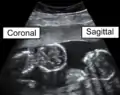

Identical twins at a gestational age of 15 weeks, shown in coronal and sagittal plane, respectively